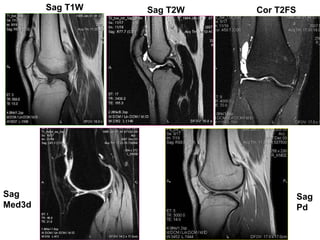

PROTOCOL CHUÏP KHÔÙP GOÁI

• Axial TIRM, PdFS

• Sagittal T2W, PdFS

• Coronal T2FS, Med3d

• Ñoä daøy laùt caét # 4mm (tröø med3d 1.5mm-20%)

• Dist. Factor # 10%

Sag

Med3d

Pd

Cor T2FSSag T2WSag T1W

Ax T2FS